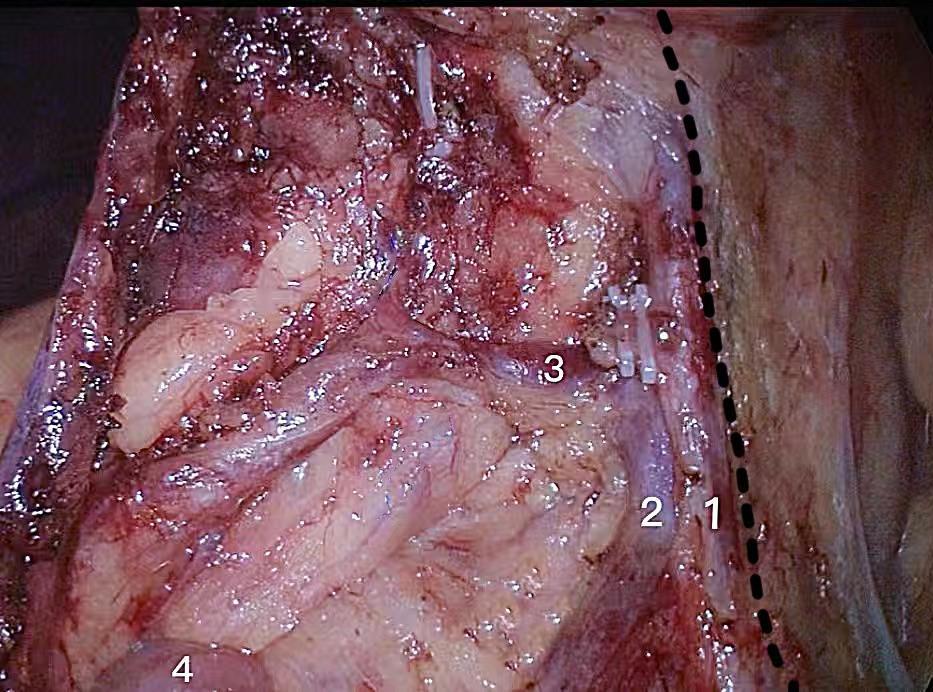

周乐其,冯波,苏浩,等. 以肠系膜上动脉左侧为右半结肠癌D3根治术淋巴结清扫内侧界可行性研究[J]. 中国实用外科杂志,2019,39(07):712-715.

陈垚,蔡丙华,朱建伟,等. 右半结肠癌根治术中全结肠系膜切除的内侧界限选择[J]. 实用临床医药杂志,2021,25(2):84-86.

ZHOU L, DIAO D, YE K, et al. The Medial Border of Laparoscopic D3 Lymphadenectomy for Right Colon Cancer: Results from an Exploratory Pilot Study[J]. Dis Colon Rectum, 2021,64(10):1286-1296. doi:10.1097/dcr.0000000000002046